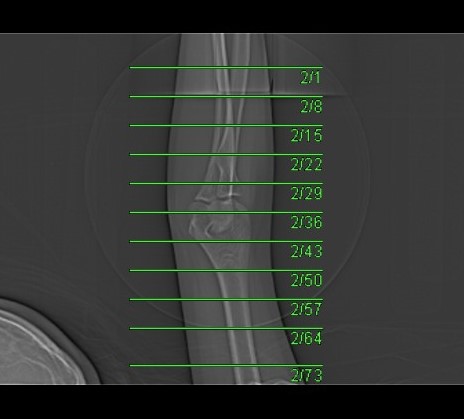

- Radial ranges of elbow